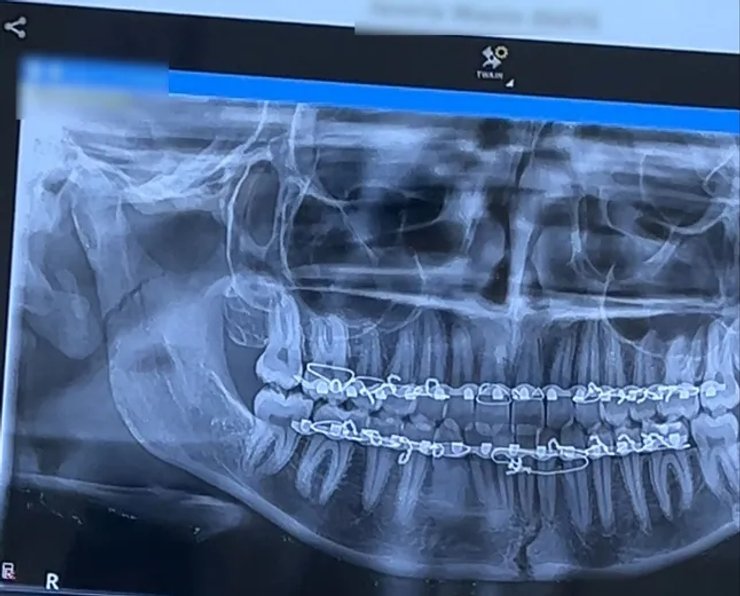

В больнице рентген и компьютерная томография показали, что у девушки два перелома челюсти.

После часовой процедуры челюсть вернули на место, а на верхнюю и нижнюю десны установили пластины, зафиксировав их проволокой на шесть недель.